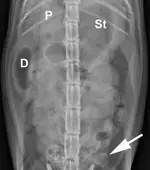

Abdominal radiography: Left/right lateral and VD views.

Radiographic Findings: The stomach (St) and duodenum (D) are severely distended with fluid and gas, suggesting intestinal obstruction or possibly pancreatitis with secondary ileus.

There is a 1.5-cm rounded opaque structure (arrows) in the caudal abdomen, to the left of the descending colon on the VD view. It is partially obscured by feces in the colon (C) on the left lateral view. The remaining organs and serosal detail appear normal.

Comments: We often perform left and right lateral radiographic views of the abdomen in cases of suspected GI foreign bodies and obstructions since the fluid and gas disperse into different portions of the GI tract. For example, any gas in the stomach rises to the pylorus (P) in left lateral recumbency and may outline a foreign body anchored to this region; this is particularly useful in suspected linear foreign bodies, which typically anchor to the tongue or pylorus and subsequently plicate varying degrees of small intestine.